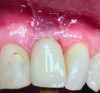

Peri-implant probing with a force of 0.25 Ncm at regular intervals is important to identify the development of peri-implant disease as well as its progression.1,10 A baseline probing depth should be recorded at the time of installation of the restoration relative to a fixed landmark on the implant or its superstructure (Figure 2).1,4 An increase in probing depth would warrant further evaluation by means of radiographs to determine the presence of bone loss surrounding the implant.1 Concerns regarding probing causing damage to the peri-implant tissue have been raised in the past; however, recent literature shows the tissue to heal within five days.10 Probing depths may vary depending on the depth of implant placement, contour of the implant, superstructure, and probing force. Hence, the initial probing depth itself should not be used as a diagnostic tool for diagnosing health and peri-implant disease, but an increase in depth over time suggests a diseased environment and the need for further evaluation.

Figure 2. Clinical probing depth: gentle probing around dental implant.

Figure 2